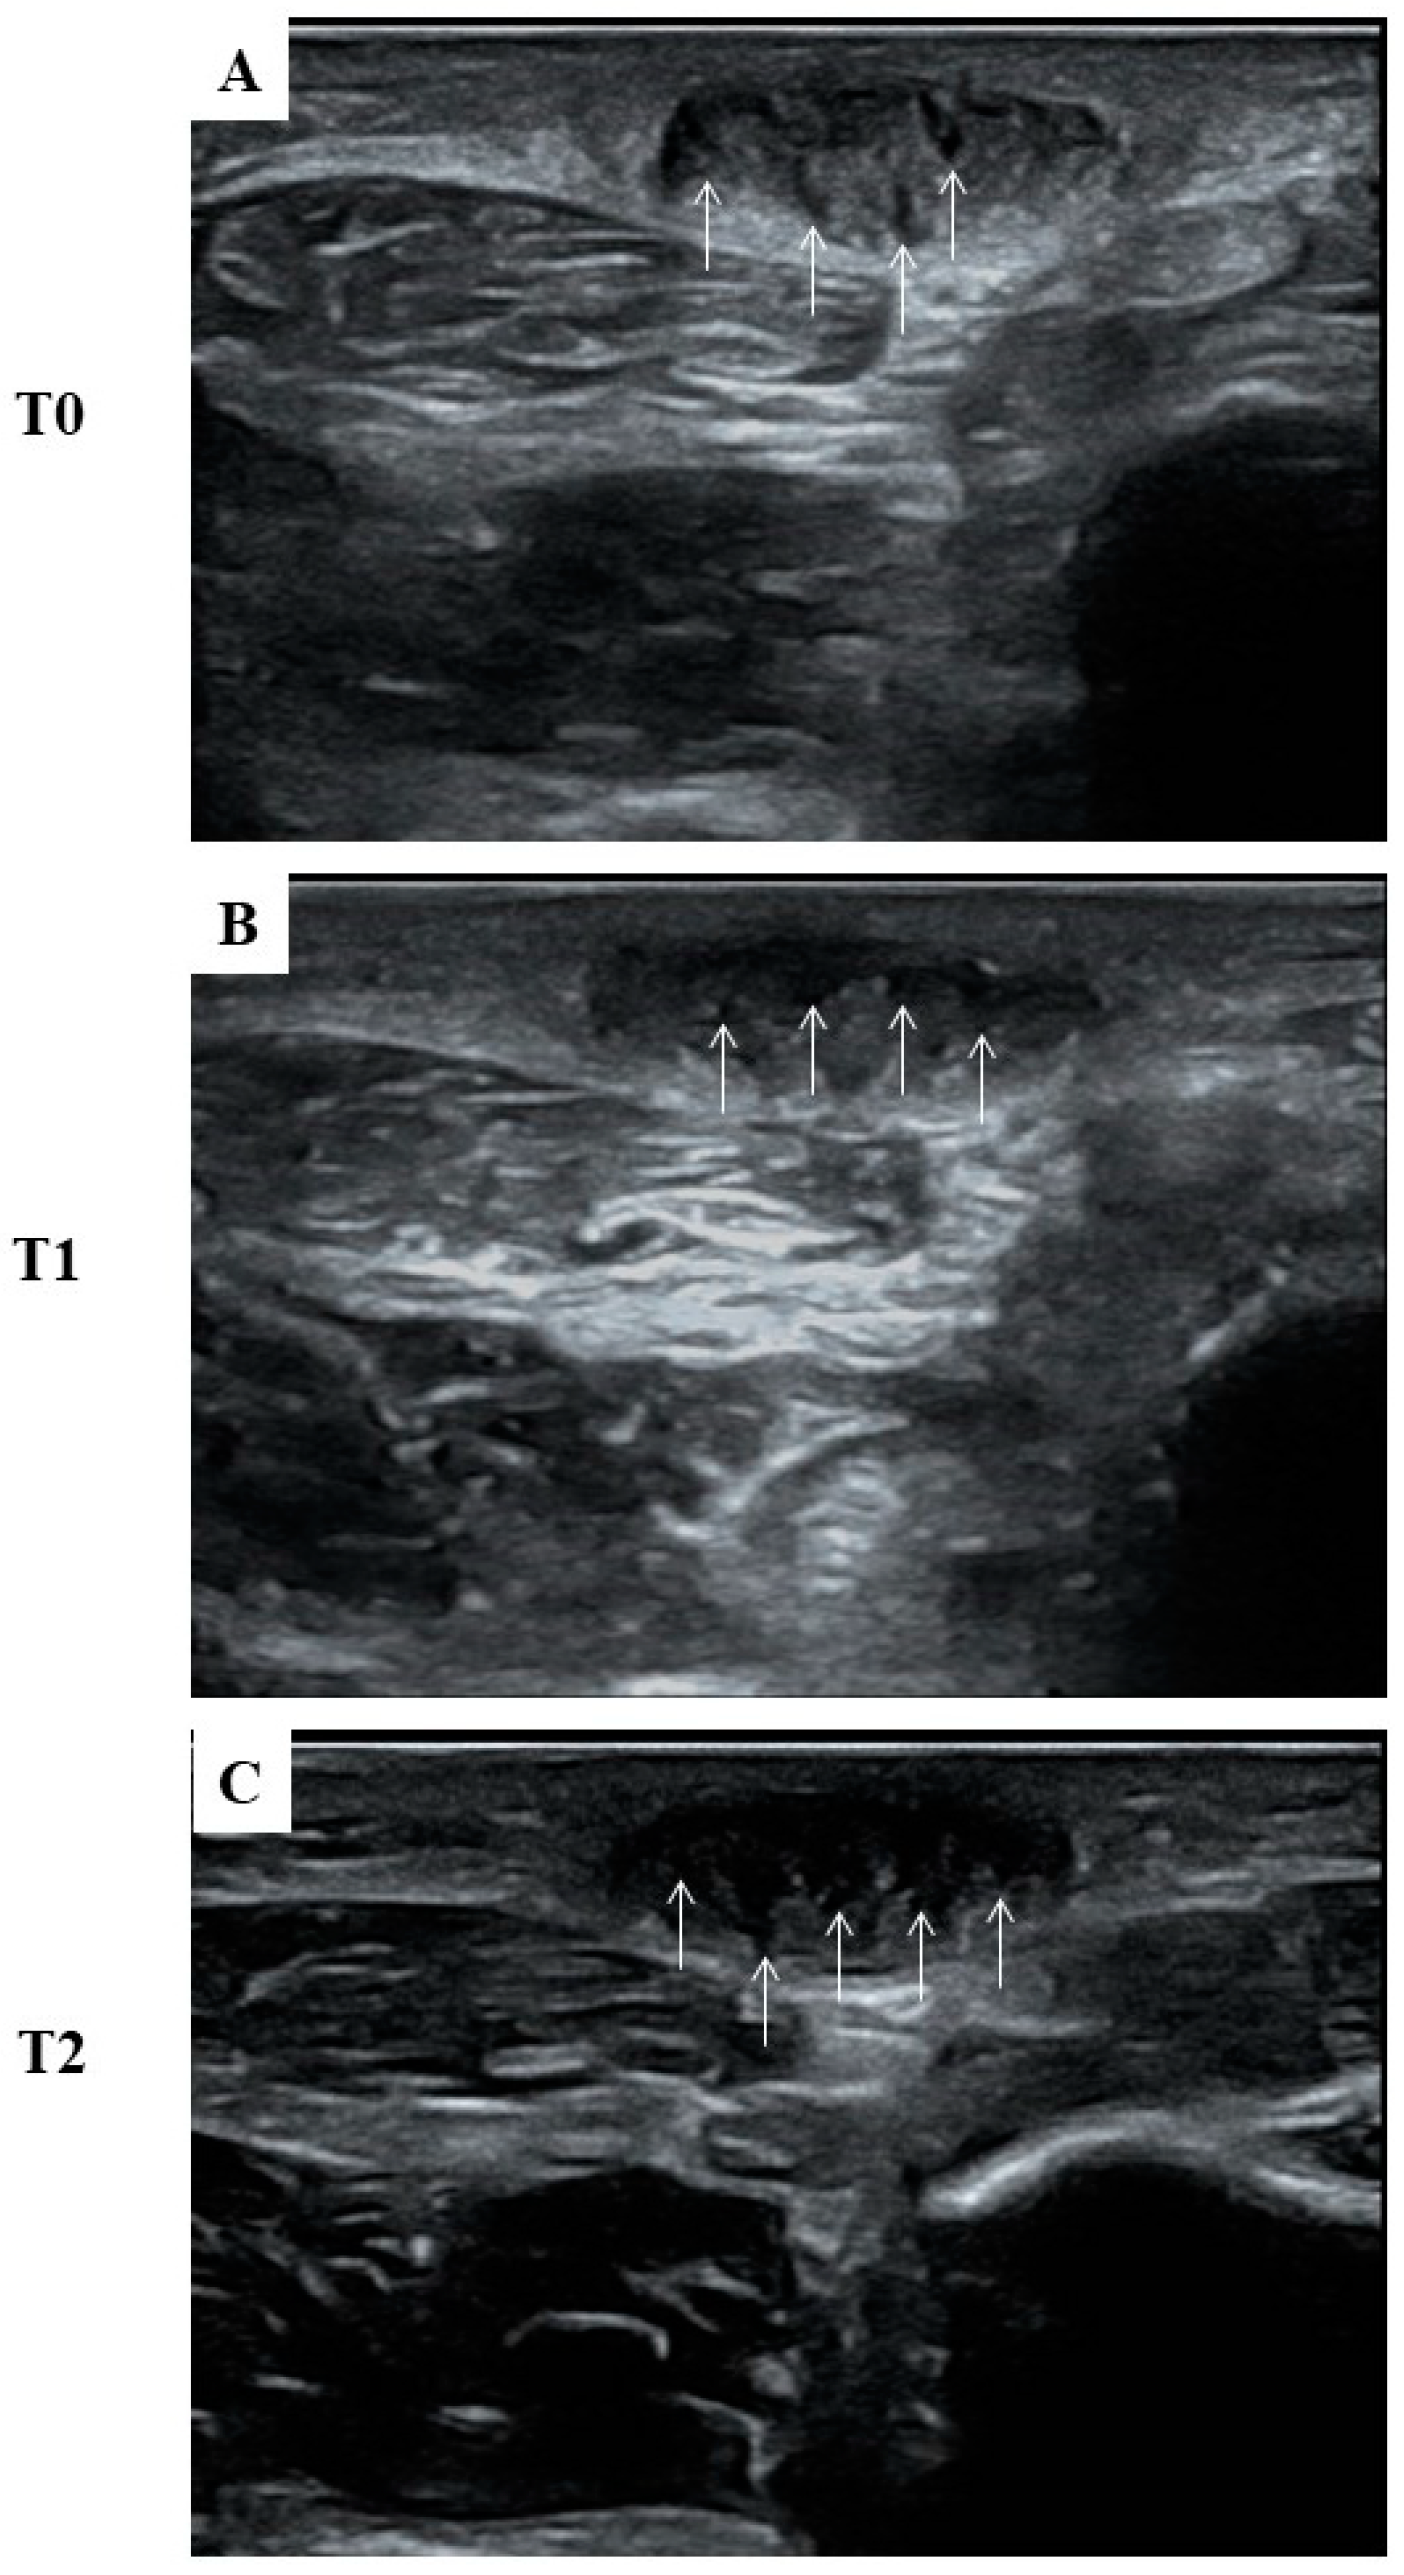

| Timing | Diameter (cm) | Echogenicity | |

|---|---|---|---|

| Maximum | Minimum | Mean Grey Value | |

| T0 | 1.46 ± 0.01 | 0.54 ± 0.01 | 0.87 ± 0.05 |

| T1 | 1.48 ± 0.02 | 0.54 ± 0.01 | 0.84 ± 0.04 |

| T2 | 1.46 ± 0.01 | 0.52 ± 0.01 | 0.50 ± 0.04 * |